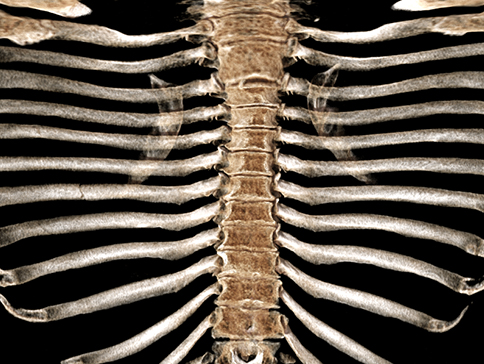

Open Rib

Open Rib is image analysis software for chest CT images. The application offers a visualization of the unfolded rib cage that allows a physician to instantly view the full rib anatomy.